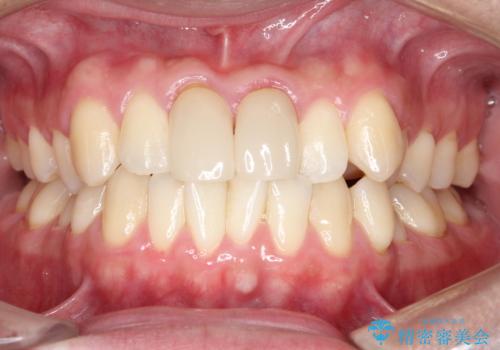

上下のがたつきをインビザラインで目立たない矯正

- 前歯のガタガタを主訴に来院されました。

上下の前歯のガタガタと左上の歯が反対にかんでいる状態でした。

上下の歯と歯の間をわずかに削り並べる計画としました。

目立たずに歯並びがよくなり、前歯に装着されたセラミックも壊さずに矯正治療が終了し満足していただけました。